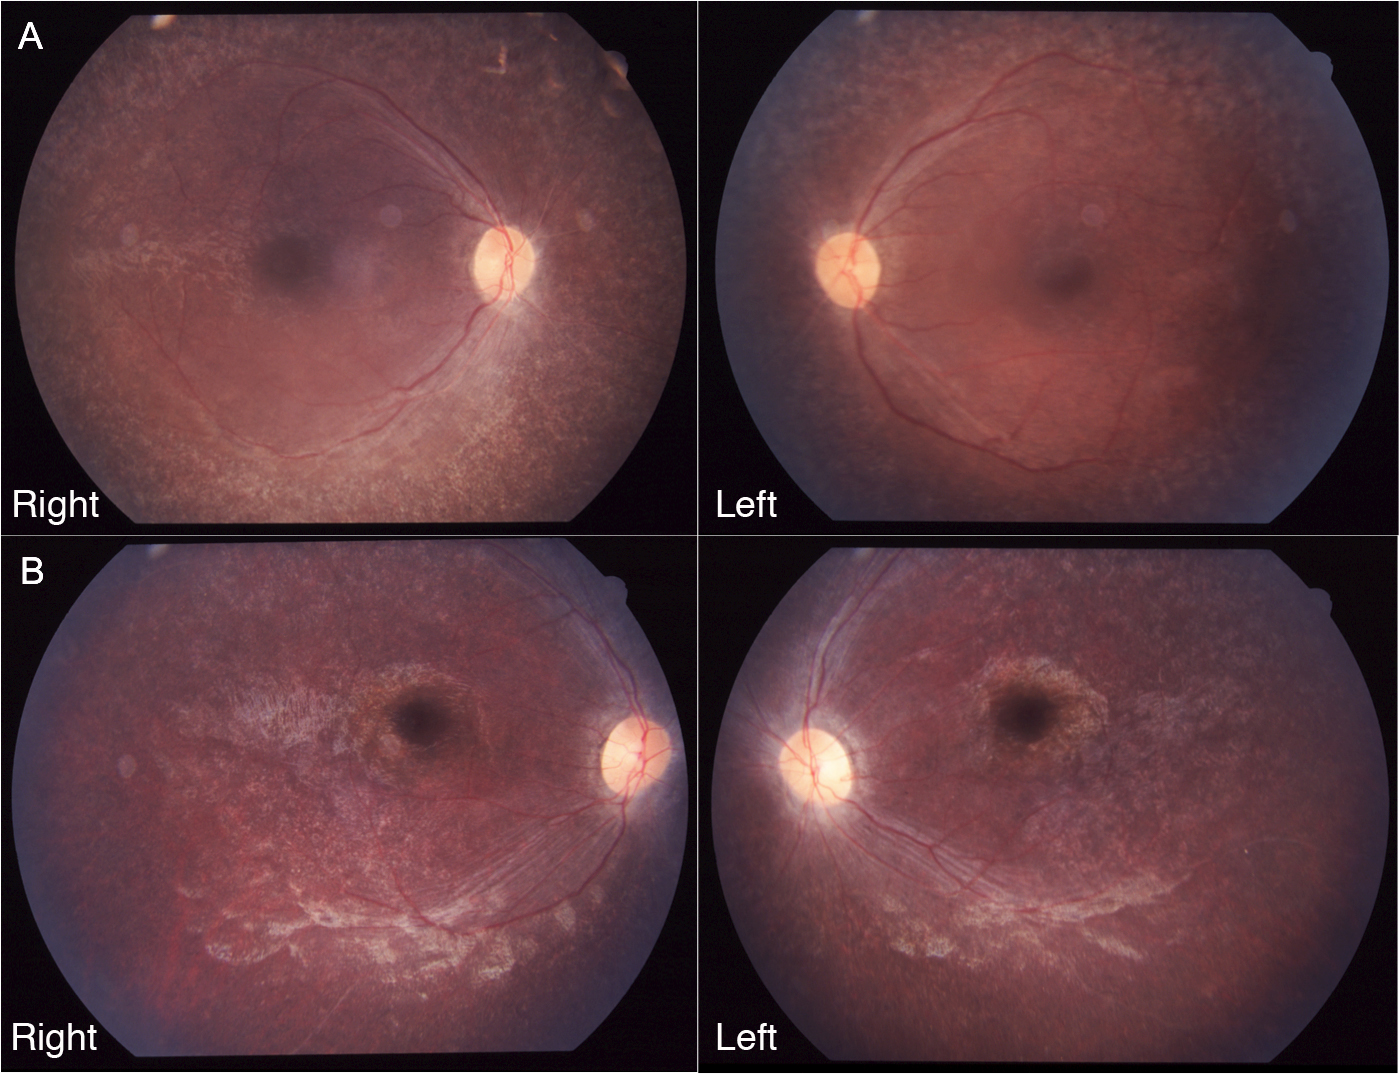

Figure 4. Fundus photographs of patients II-1 and II-2. A and B: Fundus photographs of patient II-1 at the age of 14 years (A) and patient II-2 at the age of 8 years (B) show retinal degeneration with attenuated vessels in the posterior poles of both eyes.